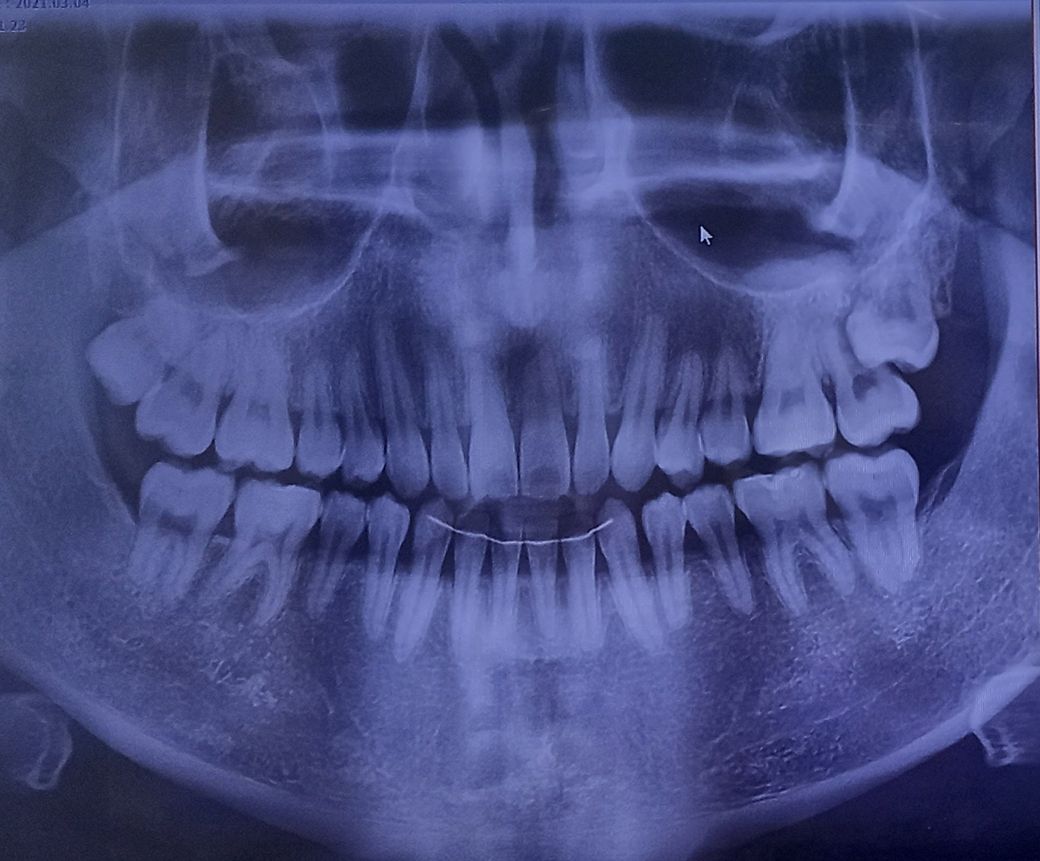

사랑니 때문에 어금니를 뽑아야 하는 상황인가요?

어금니 밑면에 충치 때문에 치과에 갔는데 사랑니와 어금니를 같이 발치하고 임플란트를 해야한다고 들었습니다.

어금니를 뽑아야 하는 상황인가요? 가능하면 신경치료 정도로 하고 제 치아를 남기고 싶습니다

• 1번 째 사진

올려주신 사진은 평면으로 나와있어 사랑니가 앞에 치아뿌리가 녹고있는건지 정확한 판단이 힘듭니다.

사랑니로 인해 뿌리가 흡수되면 발치가 고려되나 그렇지 않다면 발치가 필요없게 됩니다.

자세한 사항은 ct를 찍어 뿌리와 사랑니사이의 관계를 보는것이기 때문에 추가 검사를 추천드립니다.

올려주신 사진만 봤을때는 사랑니과 앞의 치아를 같이 빼야할 가능성이 높습니다.

더 정확한것은 씨티를 봐야 알 수 있습니다.